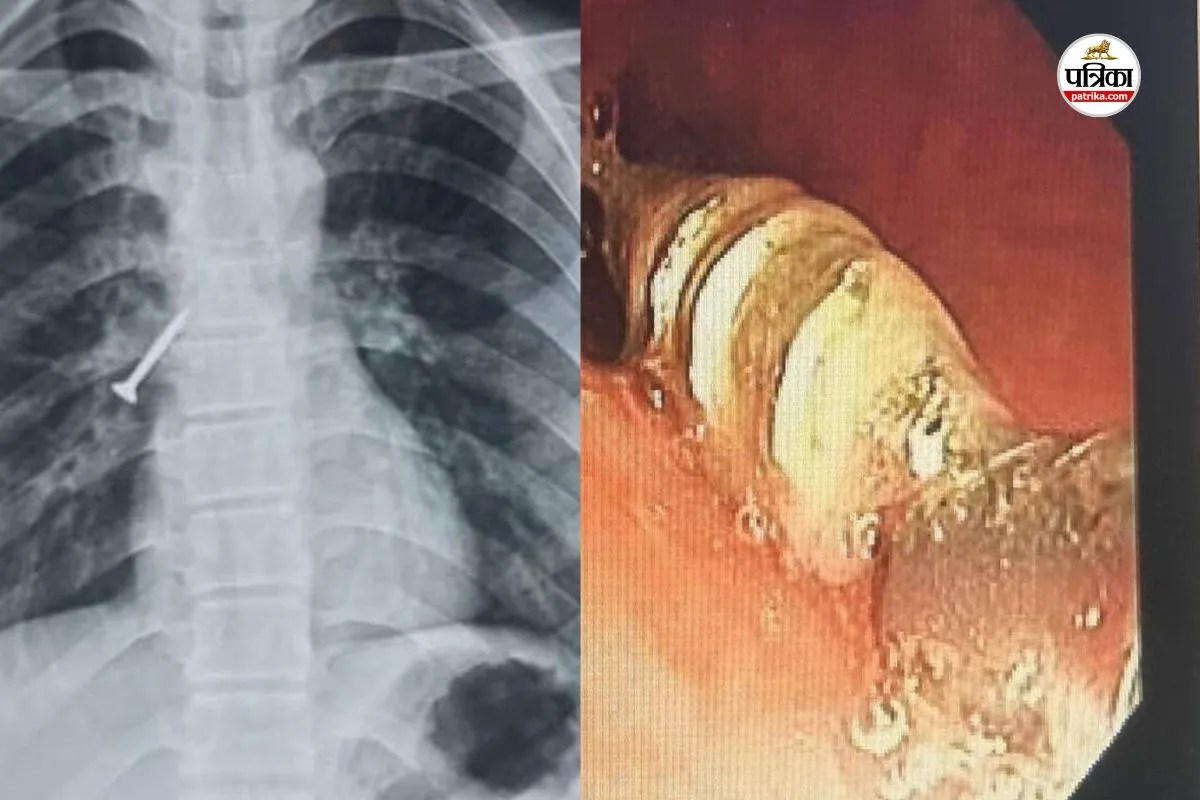

उदयपुर। आरएनटी मेडिकल कॉलेज अधीन संचालित संभाग के सबसे बड़े टीबी एवं चेस्ट अस्पताल, बड़ी के चिकित्सकों ने जटिल और जोखिम भरे मामले में 17 वर्षीय युवक की श्वास नली से 32x4 मिमी का लोहे का स्क्रू निकालकर उसे नया जीवन दिया।

यह प्रोसिजर बिना चीर-फाड़ और बिना जनरल एनेस्थीसिया के संपन्न किया। मरीज को शनिवार को अस्पताल में भर्ती किया था। स्थिति की गंभीरता देखते हुए चिकित्सकों ने तुरंत जांच कर रविवार को ‘फ्लेक्सिबल ब्रान्कोस्कोपी’ तकनीक से सफल प्रक्रिया को अंजाम दिया।

सहायक प्रोफेसर डॉ. महेश माहिच ने बताया कि युवक सुथारी का काम करते समय गलती से लंबा स्क्रू निगल गया, जो दाहिने फेफड़े की श्वास नली में फंस गया। इससे मरीज को तेज खांसी, छाती में दर्द और बलगम में खून आने जैसी गंभीर समस्याएं होने लगीं। समय रहते उपचार न मिलने पर स्थिति जानलेवा भी हो सकती थी।

सीनियर प्रोफेसर डॉ. महेन्द्र कुमार बैनाड़ा के मार्गदर्शन में टीम ने जटिल प्रक्रिया सफलतापूर्वक पूरी की। विशेषज्ञों के अनुसार, सामान्यतः ऐसे मामलों में मरीज को बेहोश कर सर्जरी या रिजिड ब्रान्कोस्कोपी की जरूरत होती है, पर टीम ने अत्याधुनिक ‘फ्लेक्सिबल ब्रान्कोस्कोपी’ का उपयोग कर न्यूनतम जोखिम में ही फंसी वस्तु को बाहर निकाल लिया।